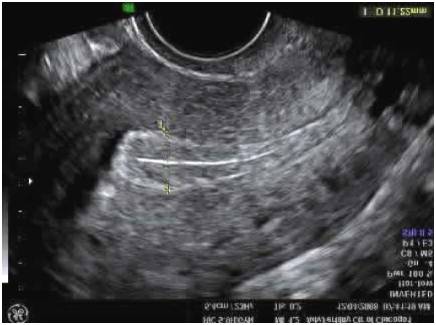

Here are some pictures of results of this ultrasound.

This is what a normal uterus looks like:

This picture actually hits close to home because you are looking at my Sonogram results. As you can see it shows that I had a polyp at the end of my uterus. So this would be considered an abnormal uterus.